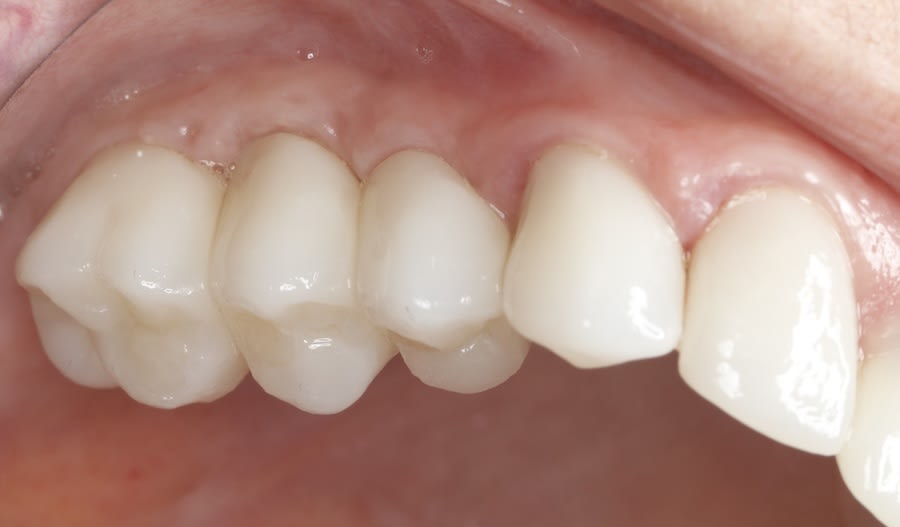

Case 1 (Figure 3 through Figure 24) depicts a 3-year follow-up of combined osseodensification sinus protocol IV in a severely resorbed maxillary ridge with ≤0.5 mm bone height in molar sites and horizontal deficiency at the first premolar site, using a two-stage approach for implant placement.

The presented protocol describes a crestal sinus elevation procedure using osseodensification burswith vertical stops (Versah) in severe cases with <2 mm of residual bone as a predictable technique, with successful bone regeneration for second-stage implant placement with subsequent stable peri-implant bone level at 3-year follow-up. This technique, thus, offers a simplified, minimally invasive, and less traumatic method for sinus floor elevation in cases with severe residual bone height loss.